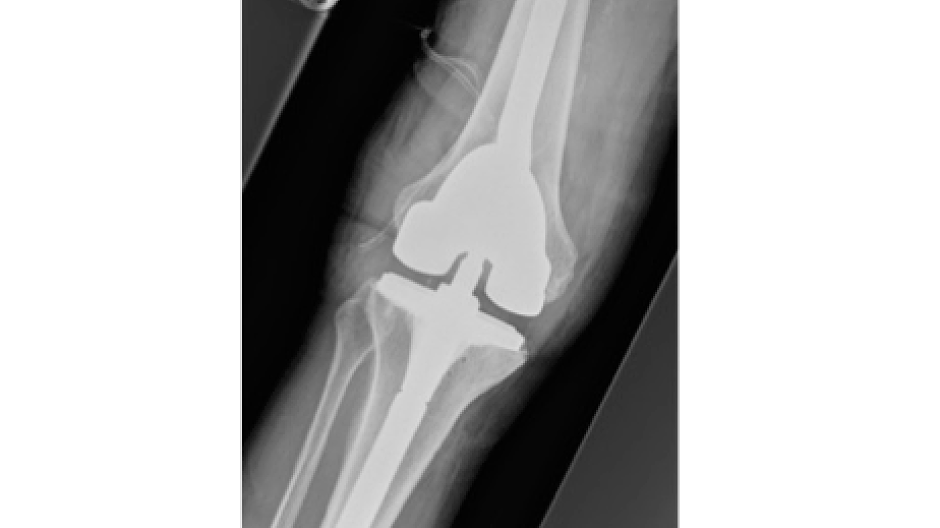

Fotos Unfallchirurgie und Orthopädie